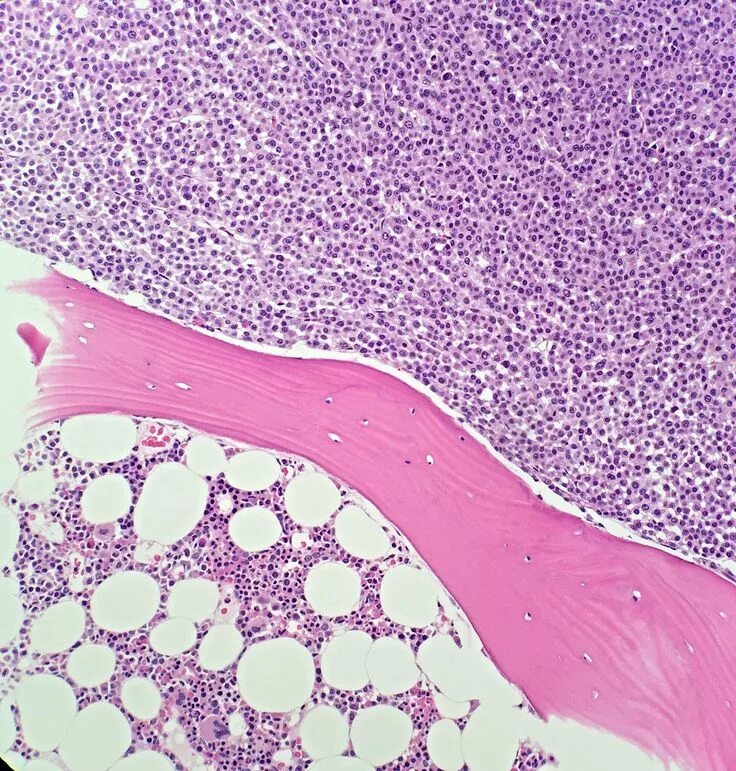

Д гистология